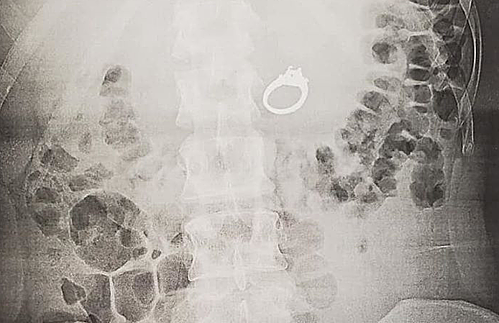

Chiếc nhẫn trong cơ thể Jenna Evans. Ảnh: Nbcsandiego.

Tại bệnh viện, Evans phải khó khăn để giải thích sự cố hài hước và khó tin của mình. Các bác sĩ khuyên nên phẫu thuật thay vì để nhẫn ra tự nhiên. Cô được gây mê và nội soi để lấy nhẫn ra.